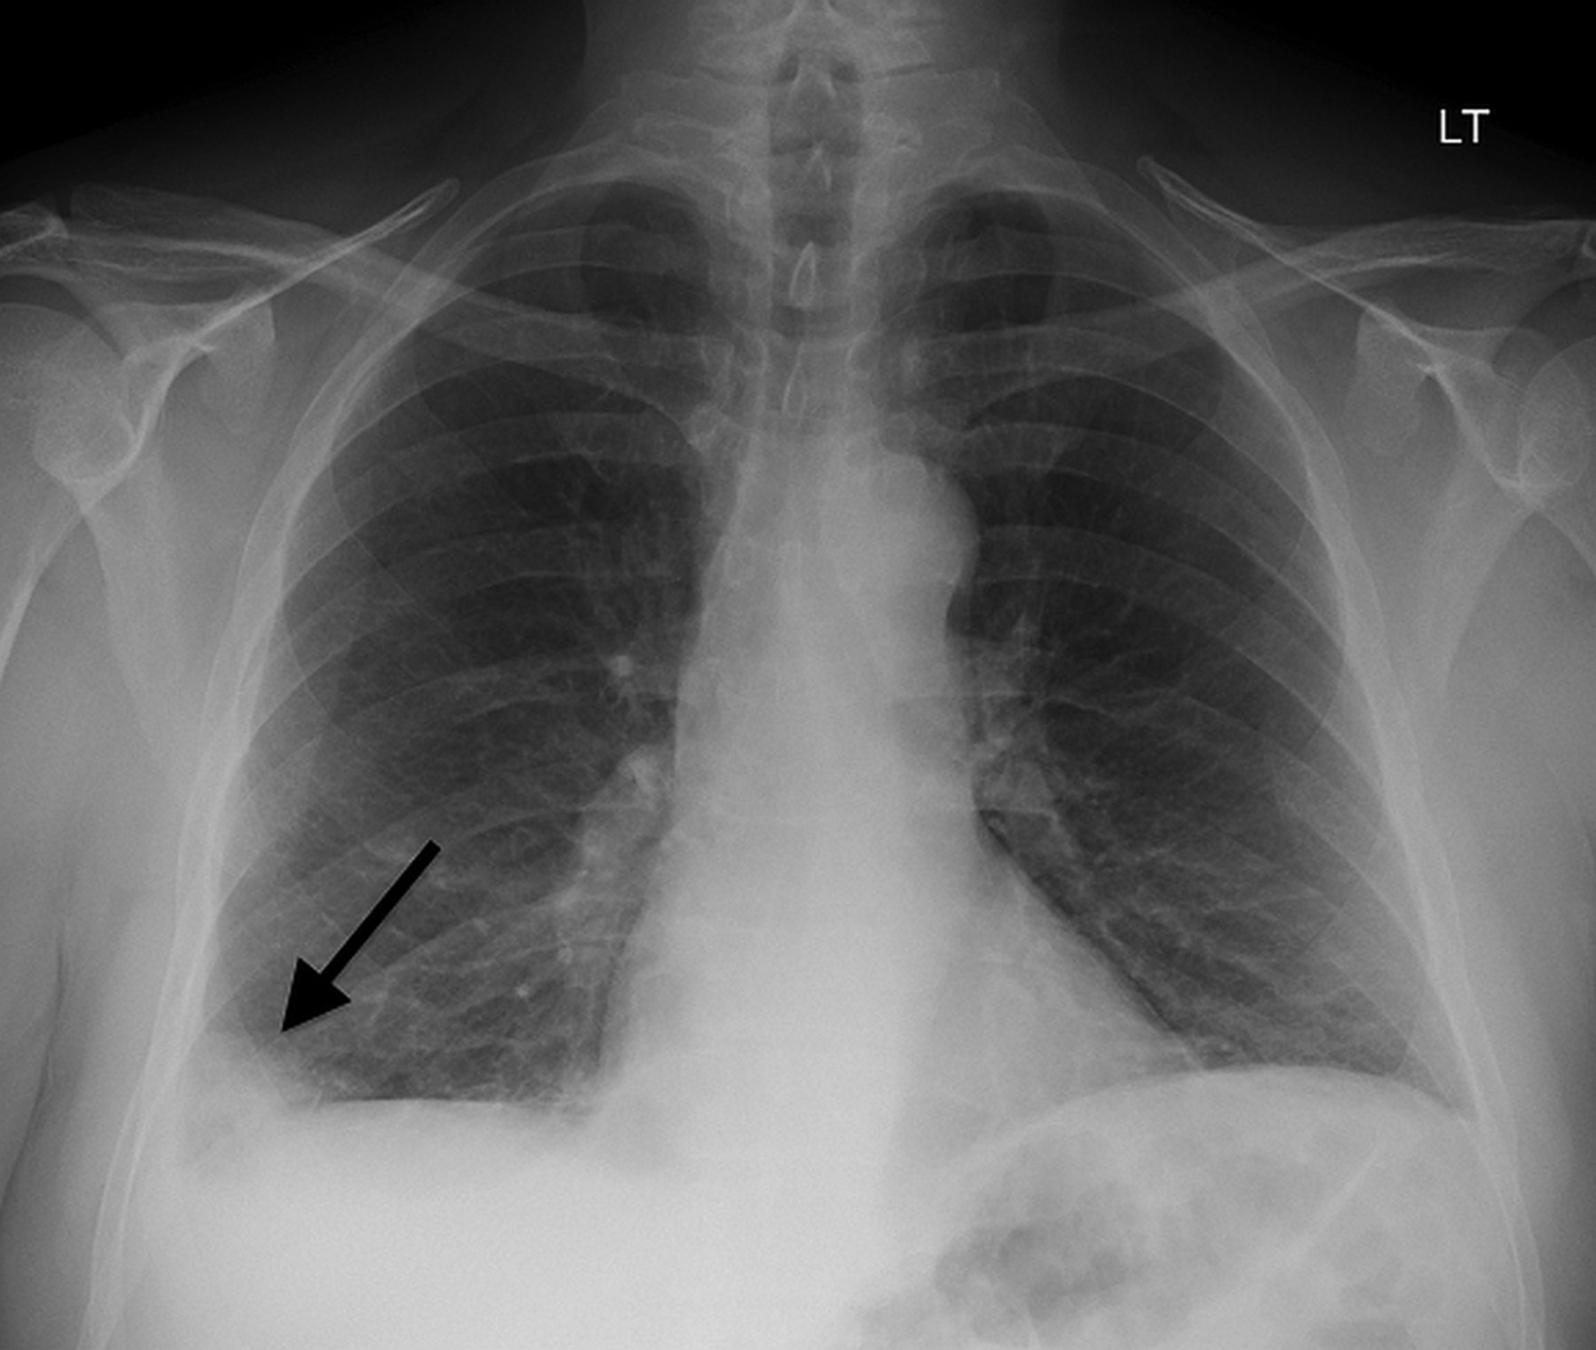

Hampton's Hump

Fleischner sign (enlarged pulmonary artery)

X-Ray Images

- sensitivity: ~22%

- specificity: ~82%

- positive predictive value: ~29%

- negative predictive value: ~76%